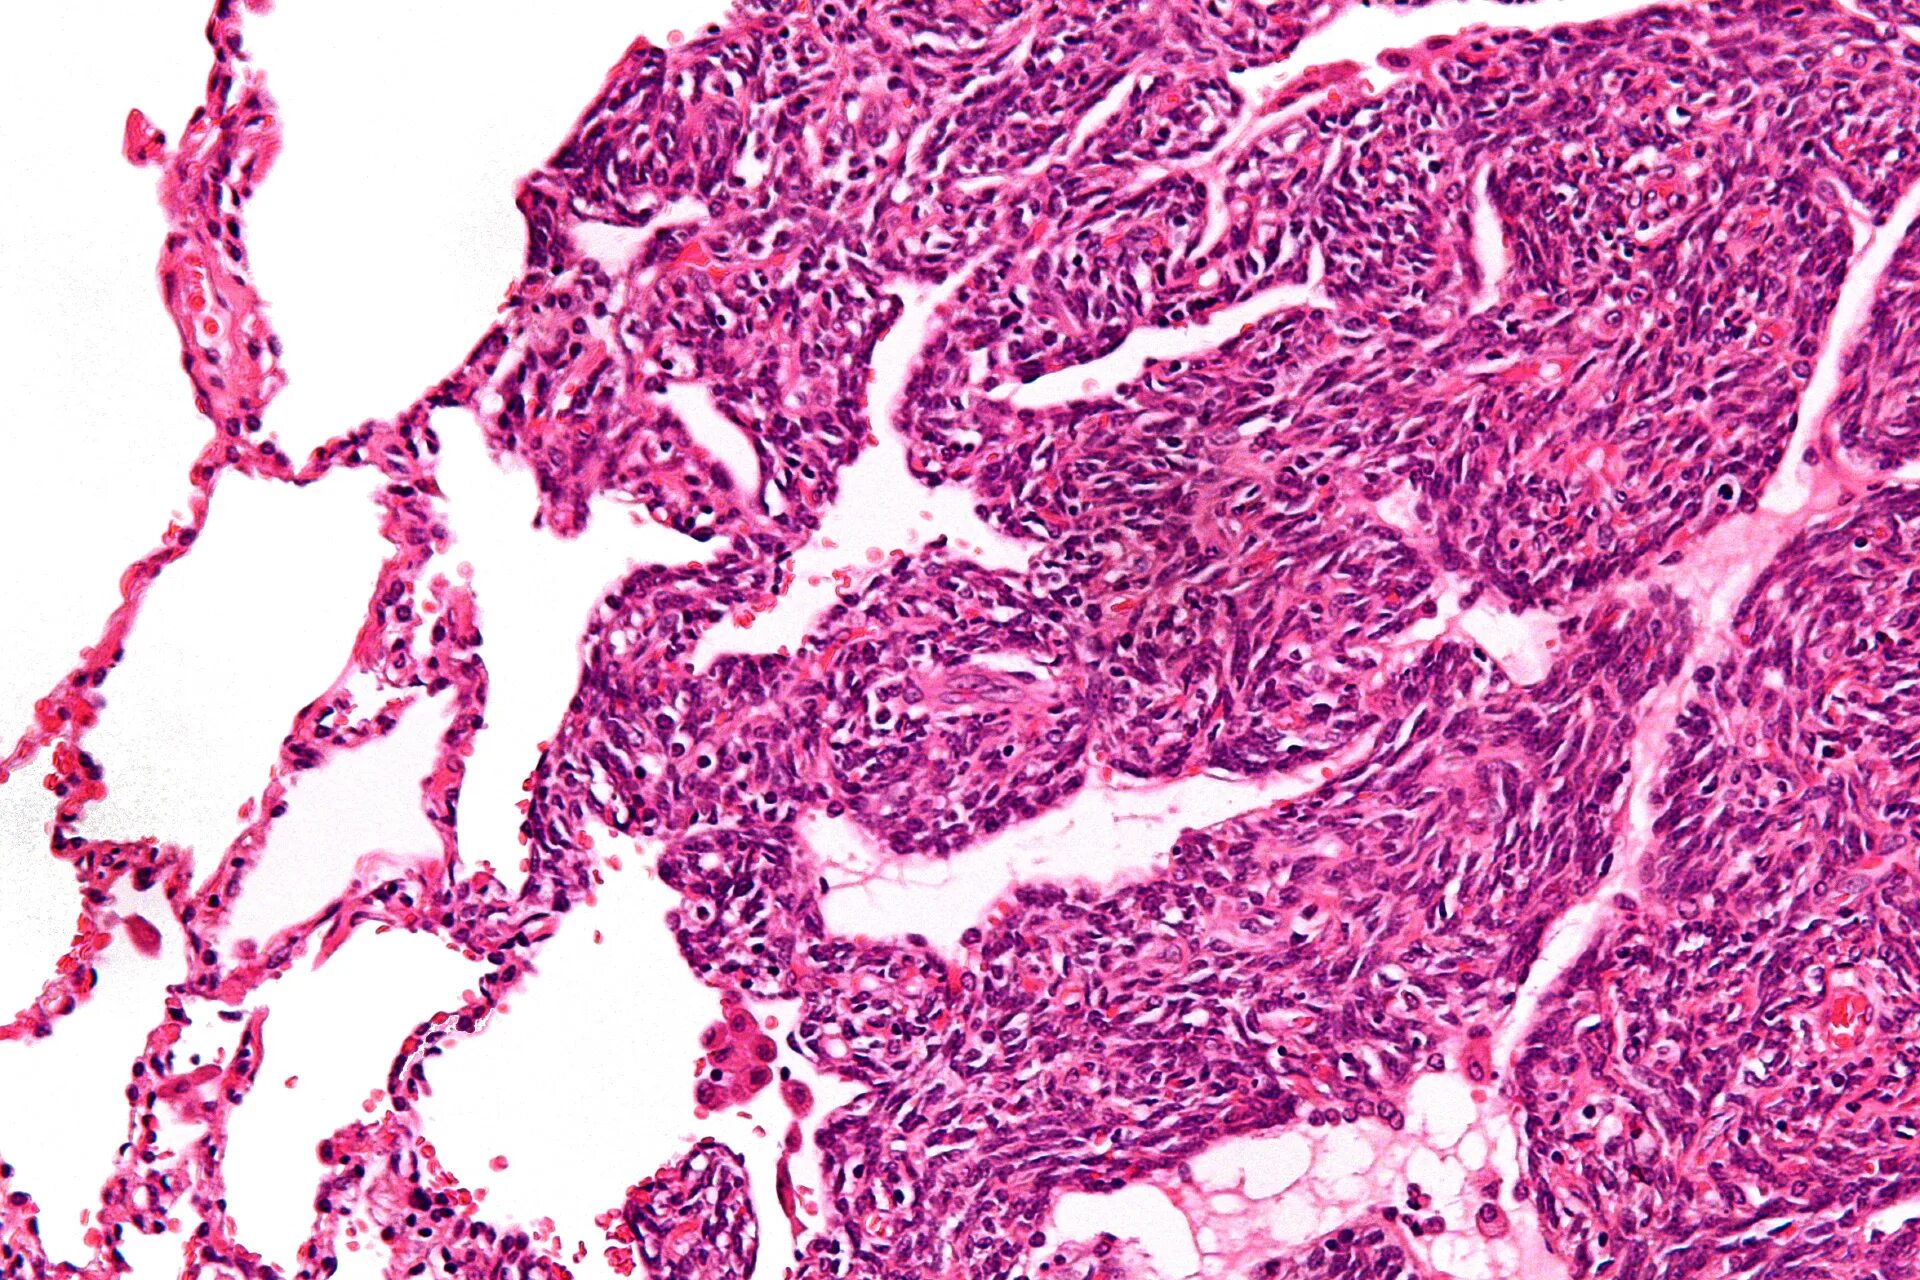

Синовиомы